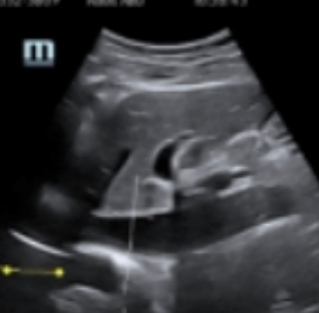

Point of care ultrasound refers to the use of ultrasound at a patient’s bedside for diagnostic or therapeutic purposes. A clinician uses point of care ultrasound (POCUS) to guide the evaluation and diagnosis in conjunction with a traditional medical examination.

A point of care ultrasound exam involves using ultrasound to answer specific clinical questions or guide a procedure at the “point of care,” whether in a hospital or a remote setting. It provides a quick, non-invasive way to speed the diagnosis and treat the patient more effectively.

Ultrasound is often used to detect intraperitoneal hemorrhage, pericardial tamponade, and hemothorax/pneumothorax – using an extended focused assessment with sonography for trauma or FAST. While POCUS of the abdomen may not allow isolating the source of the bleed, it can be helpful to determine if a bleed has occurred, which gets them into the operating room faster in many cases.